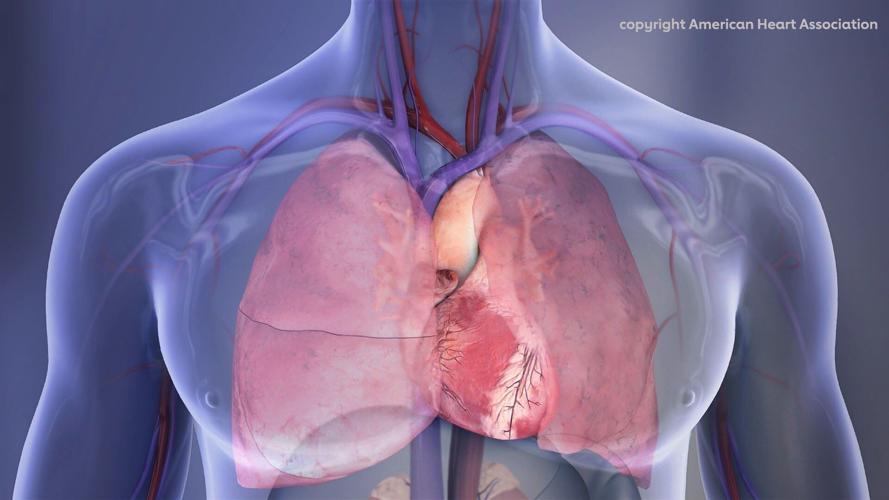

Human Chest Cavity illustration that shows the right lung, left lung and heart. (American Heart Association via SWNS)

People who stay up late and are active at night - particularly women - tend to have poor cardiovascular health scores. (American Heart Association via SWNS)